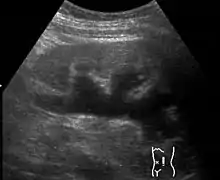

| Renal ultrasonography of hydronephrosis caused by a left ureteral stone. | |

Massive hydronephrosis as marked by the arrow.- Renal ultrasonography of hydronephrosis[14]

- Stone causing hydronephrosis[14]